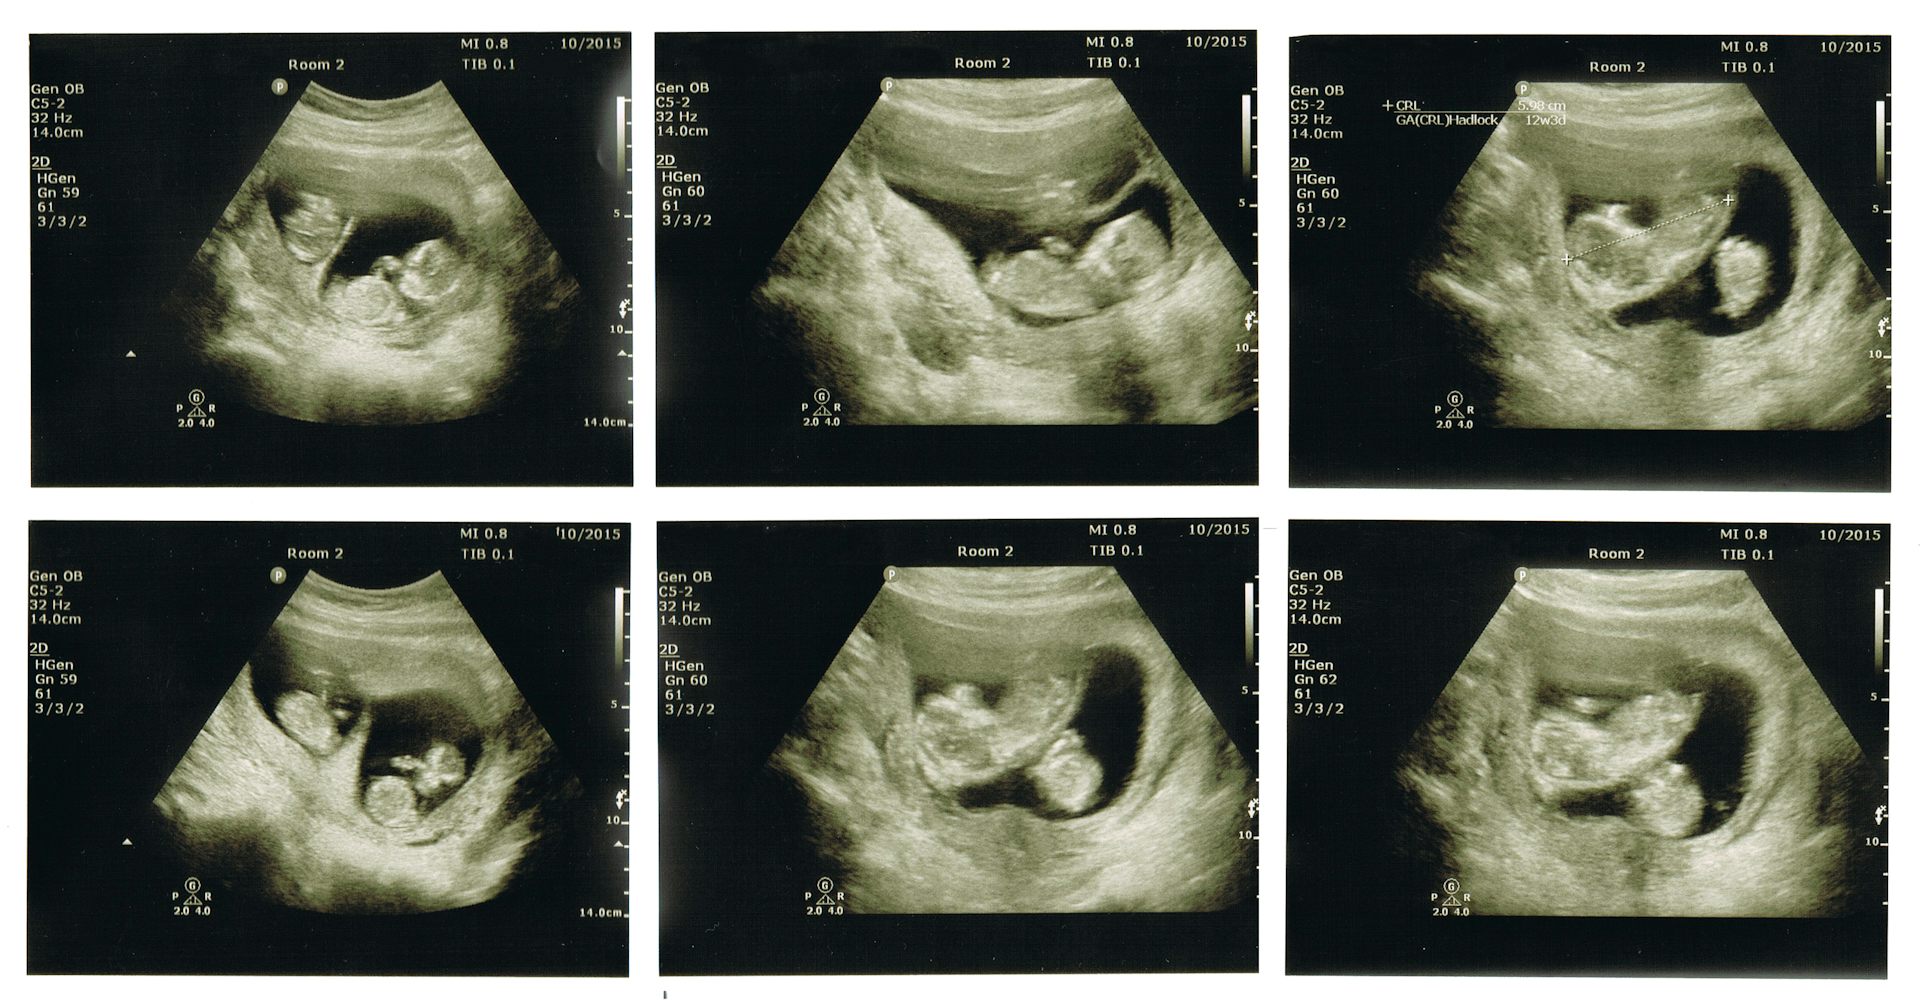

Узи расположение ребенка в матке - фото презентация